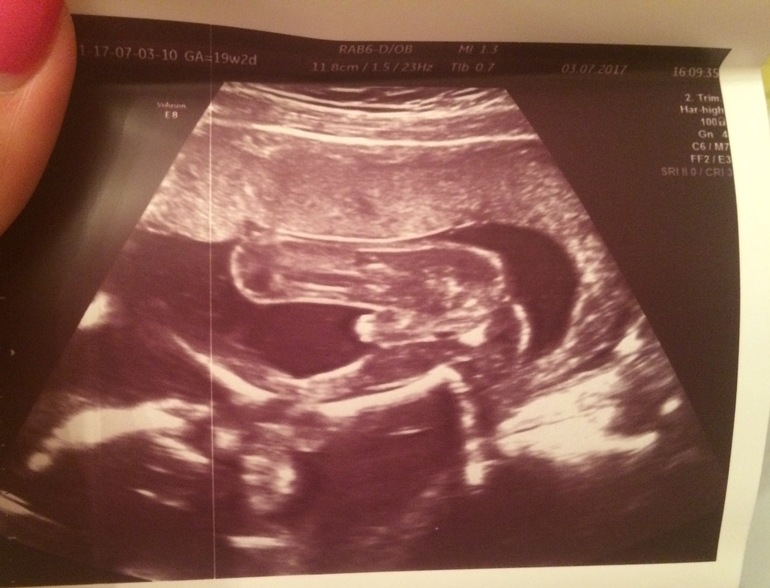

🌸Потрепала конечно нервишки себе за эти 20 недель :Dсначала выслеживала динамику ярчания тестов ,потом беготня на хгч и узи ,кстати я из тех кто чуть больше 10 раз гонял на узи и ничего ,растёт наш мальчишка здоровеньким и крепеньким !😍

(Это ножки с пипкой:))